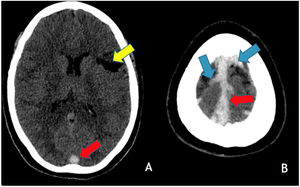

In June 2021, patient 1, at 29-years-old, went to the emergency room due to vomiting and headache and the head CT/CTV showed thrombosis of the right lateral and the superior sagittal sinuses (Fig. 4). She was admitted to the Neurology infirmary and discharged 5 days later. She remains without any neurological deficits or other sequelae and no cause for the two CVT, separated of 18 years, has been found.

Axial brain CT without contrast administration obtained 18 years after the primary event shows a left frontal cortico-subcortical vascular sequela (yellow arrow) as well as hyperdensity within the superior sagittal sinus (red arrows) and cortical veins in the high convexity (blue arrows) in keeping with recurrent cerebral venous thrombosis.